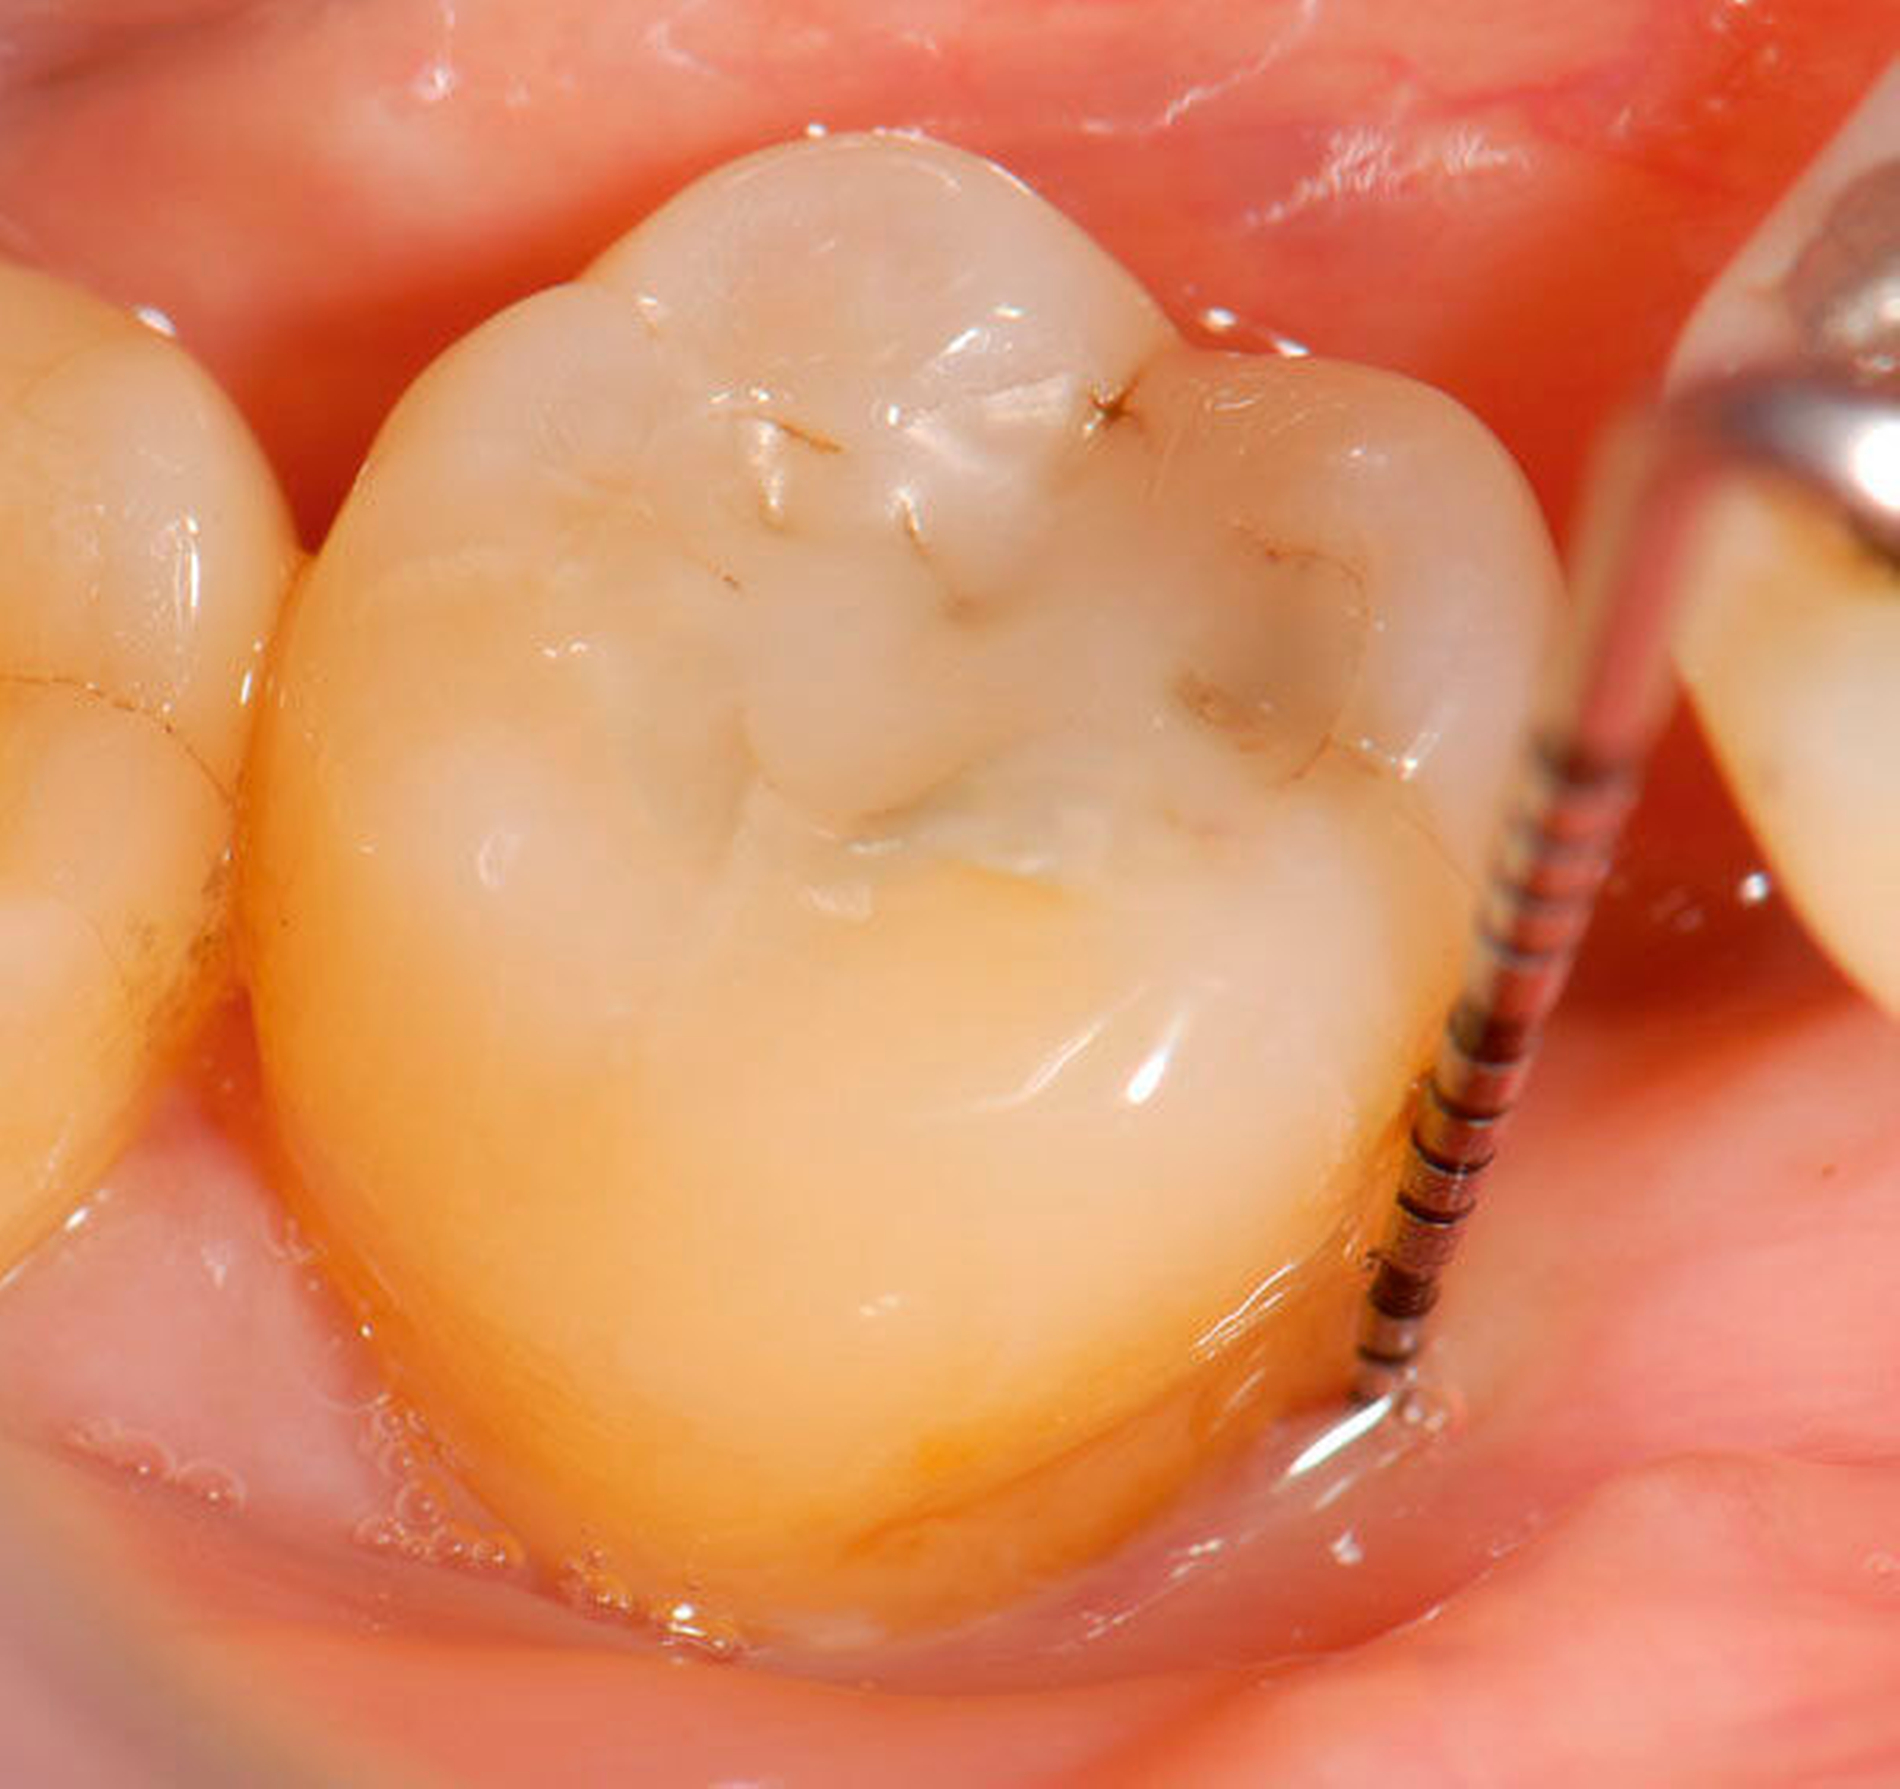

Abbildung 3: Direkte Reparatur im Seitenzahnbereich (R2-Technik)

In den Abbildungen 1 bis 3 werden Optionen für frugale Interventionen auf restaurativem Sektor aufgeführt. Es handelt sich um direkte Vollüberkronungen im Frontzahnbereich (hier: hergestellt in R1-Technik / einphasig) (Abbildung 1), direkte Teilüberkronungen im Seitenzahnbereich (hier: hergestellt in R1-Technik / einphasig) (Abbildung 2), Reparatur-Restaurationen im Seitenzahnbereich (hier: hergestellt in R2-Technik / zweiphasig) (Abbildung 3). Technische Einzelheiten zur Vorgehensweise und den Ergebnissen sind an anderer Stelle beschrieben (Literatur siehe oben).

Für die in Abbildung 2 dargestellte Situation eines tief zerstörten Prämolaren gelten ähnliche Charakteristika. Es gibt in der restaurativen Zahnheilkunde viele Neuerungen, die das Behandlungsspektrum vergrößert haben. Dazu zählen unter anderem:

ein- oder zweiphasiges Vorgehen je nach Defektausdehnungen (R1- und R2-Technik),

von Präparationsgrenzen unabhängige Verschalungstechniken, die auch bei nicht-kariesbedingten Zahnhartsubstanzschäden (wie etwa Hypomineralisationen) zum Einsatz kommen können,

schadensgerechte Reparaturtechniken (Abbildung 3),

neuartige Insertionstechniken, die unter anderem die Anpassung neuer Restaurationen an vorhandene prothetische Versorgungen (Reziproktechnik) erlauben.